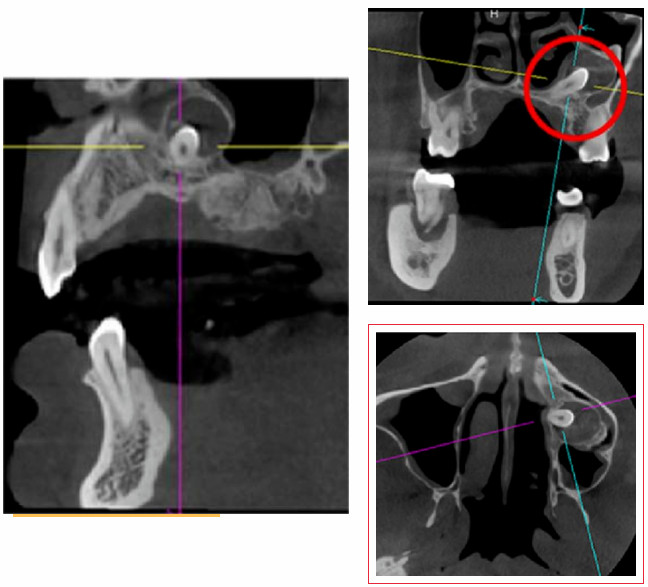

門診采用CBCT三維影像技術(shù),精準(zhǔn)定位埋伏牙位置、形態(tài)及與周圍神經(jīng)關(guān)系。根據(jù)患者口腔條件、埋伏牙位置及風(fēng)險(xiǎn)因素,定制個(gè)性化精準(zhǔn)拔牙方案,減少不必要的創(chuàng)傷與風(fēng)險(xiǎn)。